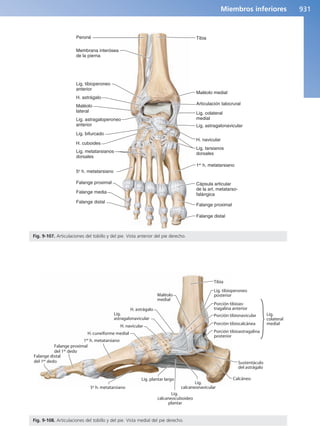

Articulaciones del pie 929